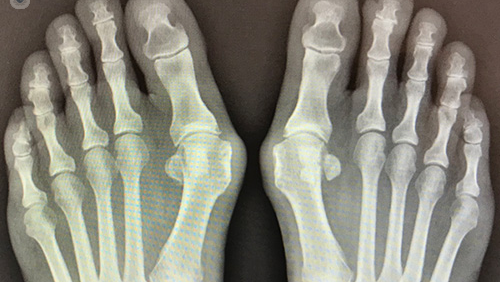

Простое упражнение при "выпирающей косточке" на ноге (Hallux valgus)